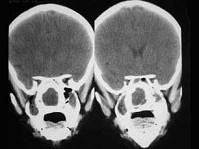

问题 女,14岁,渐进性鼻塞2年余,右眼肿痛数月,CT如图所示,应诊断为 ( )

选项 A、筛骨结核 B、筛骨骨化性纤维瘤 C、筛骨骨纤维瘤 D、筛骨软骨瘤 E、筛骨骨肉瘤

答案 B